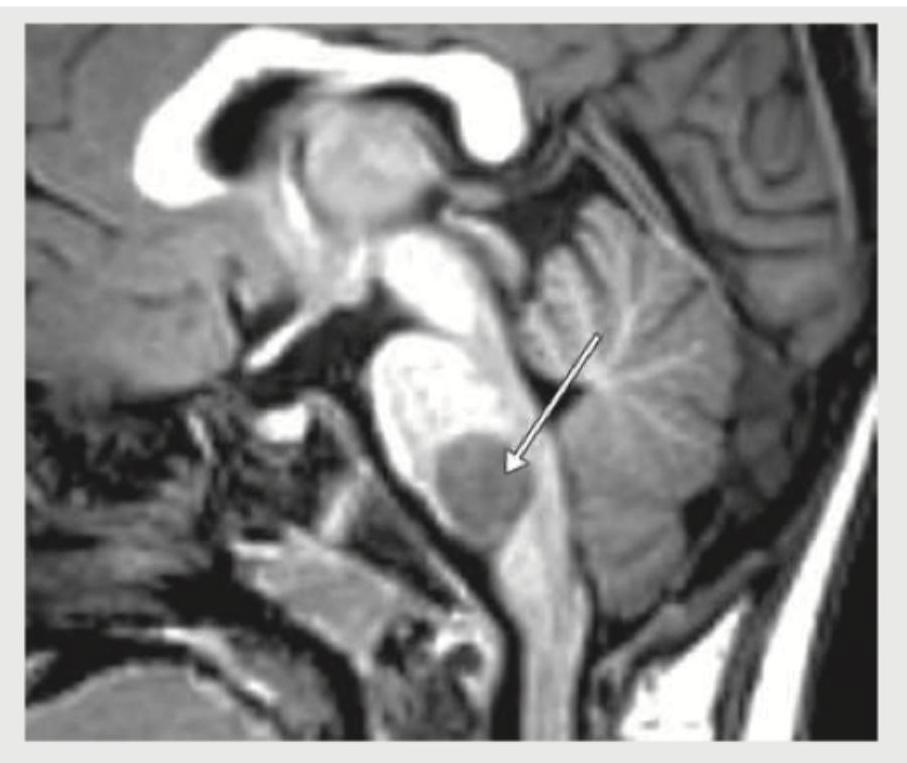

The given MRI head shows:

Explanation: ***Craniopharyngioma*** - This MRI shows a suprasellar **cystic and solid mass** with heterogeneous signal intensity, which is characteristic of a craniopharyngioma. - The location extending into the **third ventricle** and the heterogeneous nature with possible calcifications (though not clearly visible in this T1 image) are typical features. *Pontine glioma* - A **pontine glioma** would be located within the **pons** (part of the brainstem), typically showing an expansive lesion intrinsic to the brainstem. - The lesion in the image is clearly suprasellar and not originating from the pons. *Cerebellar astrocytoma* - A **cerebellar astrocytoma** would be located within the **cerebellum**, in the posterior fossa, commonly presenting as a cystic lesion with a mural nodule. - The pictured mass is above the sella turcica, indicating a supratentorial location, and not within the cerebellum. *Pinealoma* - A **pinealoma** arises in the **pineal gland** region, posterior to the third ventricle and superior to the superior colliculi. - The lesion in the image is anterior to this location, in the suprasellar cistern and extending into the third ventricle, which is not consistent with a pinealoma.